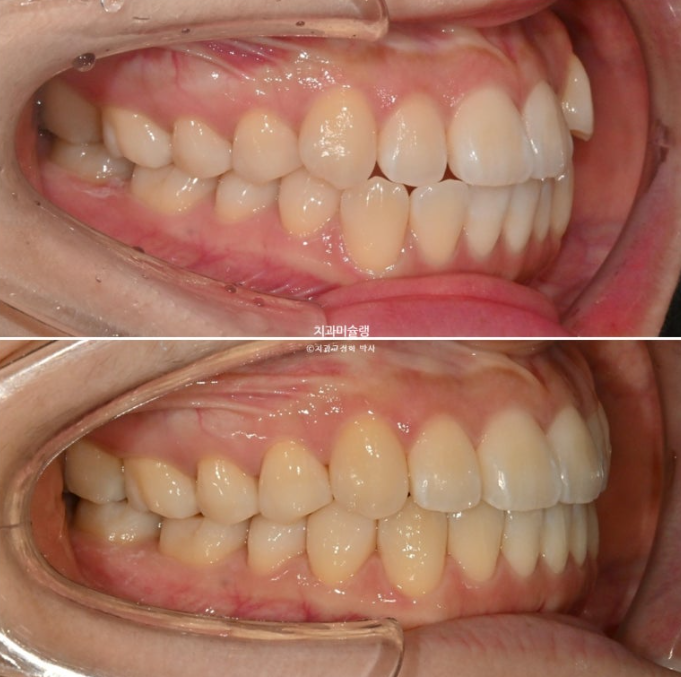

25.03~25.12

앞니 뻗침의 미세한 개선

아래 앞니가 뒤로 들어가면서 아랫입술이 소량 후방이동 했고 따라서 큰 변화는 아니지만 입매는 묘하게 예뻐졌습니다. 뚱한 느낌이 사라졌다고 표현을 합니다.